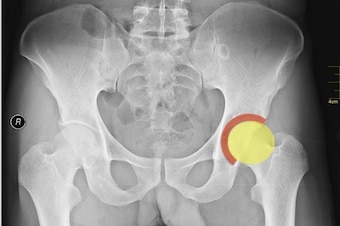

A "slight tear" in Percy Harvin's acetabular labrum cost the Seahawks wideout almost all of the 2013 season, and until recently, it threatened his postseason as well.

The "hip" marks the point where the femur (or thigh bone) meets the pelvis. Specifically, the rounded head of the femur sits within the cup-like acetabulum—or hip socket.

Around the rim of the acetabulum sits a cartilaginous labrum.

By encircling the acetabulum, the labrum deepens the cup inside which the head of the femur rests. As a result, the femur sits more snugly and is less able to fall out of the socket—a dislocation.